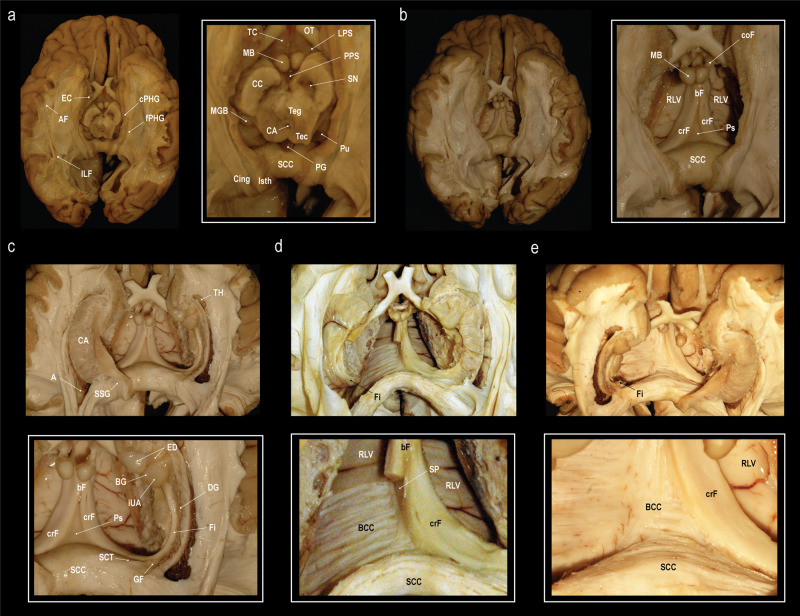

Multidirectional ex vivo fiber dissection

The subsplenial region between the forniceal crura, where the forniceal commissure would be expected, was approached in a stepwise fashion. Fiber dissection was performed from ventral to dorsal, dorsal to ventral, and from caudal to rostral.

Dissection from ventral to dorsal (Fig. 3): The entorhinal cortex as well as the cortex from the parahippocampal and fusiform gyri was peeled away, and the arcuate fibers were removed to expose the fibers of the parahippocampus and the inferior longitudinal fasciculus (Fig. 3a). The mesencephalon, the thalamus, part of the hypothalamus and the caudate nucleus were removed to expose the columnae, body and crura of the fornices, and the roof of the lateral ventricles (Fig. 3b). To expose the fimbria, the fibers of the parahippocampal gyrus and the inferior longitudinal fasciculus were removed as well as part of the cornu ammonis and the ependyma of the floor of the atrium and temporal horn (Fig. 3c). The fornix was then dissected from the dorsal end of the fimbria along the crus towards the body (Fig. 3d). By the end of the dissection the body of the corpus callosum was exposed (Fig. 3e). We were able to identify the psalterium as a thin soft tissue membrane spanning between the right and left crus fornicis in all specimens. It was limited rostrally by the merging bodies of the fornix, rostro-dorsally by the septum pellucidum, dorso-caudally it attached to the splenium of the corpus callosum and ventrally it abutted the velum interpositum. We were, however, unable to identify any crossing fibers between the crura fornicis.

Fig. 3. Fiber dissection from the ventral aspect.

Stepwise fiber dissection of the subsplenial region from the ventral towards the dorsal surface of the cerebrum after brain preparation following a modified Klingler technique. a Exposure of the inferior longitudinal fasciculus (ILF) and the fibers of the parahippocampal gyrus (fPHG) after removal of the entorhinal cortex (EC), cortex of the parahippocampal (cPHG) and fusiform (lateral to the PHG, not shown) gyri and the underlying arcuate fibers (AF). CA cerebral aqueduct, CC crus cerebri, Cing cingulum, Isth isthmus, LPS lateral perforated substance, MB mammillary body, MGB medial geniculate body, OT optic tract, PG pineal gland, PPS posterior perforated substance, Pu pulvinar, SCC splenium of the corpus callosum, SN substantia nigra, TC tuber cinereum, Tec tectum mesencephali, Teg tegmentum mesencephali. b View on the roof of the lateral ventricles (RLV), crus (crF), body (bF) and column (coF) of the fornix, and the psalterium (Ps) after removal of the mesencephalon, thalamus, and parts of the hypothalamus and the caudate nucleus. c Exposure of the dentate gyrus (DG), fimbria (Fi), gyrus fasciolaris (GF), the subcallosal trigone (SCT), inferior surface of the uncal apex (iUA), band of Giacomini (BG), and the external digitations of the hippocampal head (ED) after removal of the fibers of the parahippocampal gyrus, inferior longitudinal fasciculus, part of the cornu ammonis (CA) and the ependyma of the floor of the atrium (A) and the temporal horn (TH). d, e Dissection of the fornix from the dorsal end of the fimbria (Fi) along the crus (crF) towards the body of the fornix (bF). Dissection of the body of the fornix (bF) reveals the septum pellucidum (SP). No commissural fibers between the fornicis were identified. Removal of the ependymal layer of the roof of the lateral ventricle (RLV) exposed the fibers of the body of the corpus callosum (BCC). Dissections: NK.

Dissection from dorsal to ventral (Fig. 4): Both hemispheres were cut down to the level of the corpus callosum, exposing the supracommissural hippocampus. The callosal fibers were removed layer by layer until the ventricles, the septum pellucidum, and the crus fornicis were shining through. On one side the ventricle was opened to identify the caudate nucleus, the choroid plexus, and crus and body of the fornix. The removal of the remaining callosal fibers was performed and the underlying psalterium dissected without identification of crossing fibers between the fornices.

Fig. 4. Fiber dissection from the dorsal aspect.

a Exposure of the corpus callosum (CC) and the supracommissural hippocampus with its medial longitudinal stria (MLS), lateral longitudinal stria (LLS) and the indusium griseum (IG). b Removal of the fibers of the body of the corpus callosum (BCC) until the lateral ventricle (LV), the crus fornicis (CF), and the septum pellucidum (SP) were shining through (right). Further dissection of the remaining callosal fibers and removal of the choroid plexus and lamina affixa revealed the taenia fornicis (TF), thalamus (Th), lamina terminalis (LT) and the caudate nucleus (CN) (left). c Elevation of the psalterium (Ps) without identification of commissural fibers between the crura fornicis (CF) revealed the velum interpositum (VI). The choroid plexus (CP) is fixed to the crus fornicis via the taenia fornicis (TF) and to the lamina affixa (LA) through the taenia choroidea (TC). The thalamus (Th) is shining through the choroid plexus and the lamina affixa. d Different specimen, where the SP and Ps was left intact on the left side, but on the right the CP and LA were removed to expose the Th and the choroidal fissure (FC). Dissection of the right CN revealed the underlying fibers of the internal capsule (IC). Stripping of the ependyma in the atrium (A) exposed the fibers of the forceps major (FM). The calcar avis (CA) is formed by the underlying sulcus calcarinus. Starting from the SCC and running over the atrium are the fibers of the tapetum (Ta). e Anterior oblique view on the same specimen (before dissection of the CN). The fibers of the FM create the bulb of the posterior horn (B). Dissections: NK (A-C) and CS (D-E).

Dissection from caudal to rostral (Fig. 5a–g): The hemispheres were reduced up to the splenium of the corpus callosum. The splenium was fenestrated to visualize the lateral ventricle, the crus fornicis and the psalterium. In the midline, the callosal fibers were separated and elevated from the psalterium. There were no fibers identified crossing from one crus fornicis to the other.

Fig. 5. Fiber dissection from the caudal aspect and morphometry of the psalterium.

a Exposure of the splenium of the corpus callosum (SCC) and the quadrigeminal plate (QP) after bilateral removal of the medial aspects of the occipital lobes and the cerebellar apex. b Closer view on the SCC, the pineal gland (PG), and the superior (SC) and inferior colliculi (IC) with the corresponding brachia (brachium of the superior colliculus, Bsc; brachium of the inferior colliculus; Bic) c Dissection of the subcortical fibers of the right isthmus revealed the fibers of the forceps major (FM) as caudo-lateral continuation of the SCC. In addition, the cerebral peduncle (CPe), medial geniculate body (MGB) and lateral geniculate body (LGB) are exposed. d Posterior oblique view on the crus fornicis (crF), the choroidal fissure (FC), and the pulvinar (Pu) after opening the atrium (A). e Midline incision and removal of the right half of the SCC exposes the septum pellucidum (SP), velum interpositum (VI), the tapetum (Ta) passing over the A, the crF, and the choroid plexus (CP). f Another specimen after fenestration of the SCC and partial removal of the thalamus (Th) to visualize the A, crF and psalterium (Ps). g Separation and elevation of the medial part of the SCC from the Ps. The unification of the crF into the body of the fornix (bF) form the anterior border of the Ps. h The length (l) of the Ps was measured from the unification of the crF to form the bF to the SCC. The width (w) of the Ps was defined as the distance between right and left attachment of the crF to the SCC. Dissections: CS (A-E), KA (F-G), and NK (H).

Based upon the measurements in nine human specimens (Table 1), the psalterium had a mean length of 1.4 cm (SD 0.40 cm) and a mean width of 2.4 cm (SD 0.51 cm) (Fig. 5).

In summary, the psalterium was visualized in all human brain specimens as a soft tissue membrane that spans between the two crus fornicis and is bounded rostrally by the union of the crus fornicis to form the body of the fornix, rostro-dorsally by the septum pellucidum, dorso-caudally by the splenium of the corpus callosum, and ventrally by the velum interpositum. It was not possible to identify commissural fibers between the two crura fornicis by further dissection of this membrane.